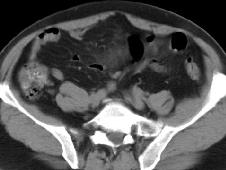

原发性肠系膜肿瘤的发病率虽不高,多见于男性,男女比为3:2或2:1,可发生于任何年龄,但个别胚胎组织残留来源的肿瘤,多见于儿童及青少年,大部分原发性肠系膜肿瘤来源于间叶组织及神经组织,其中以淋巴肉瘤发病率最高。